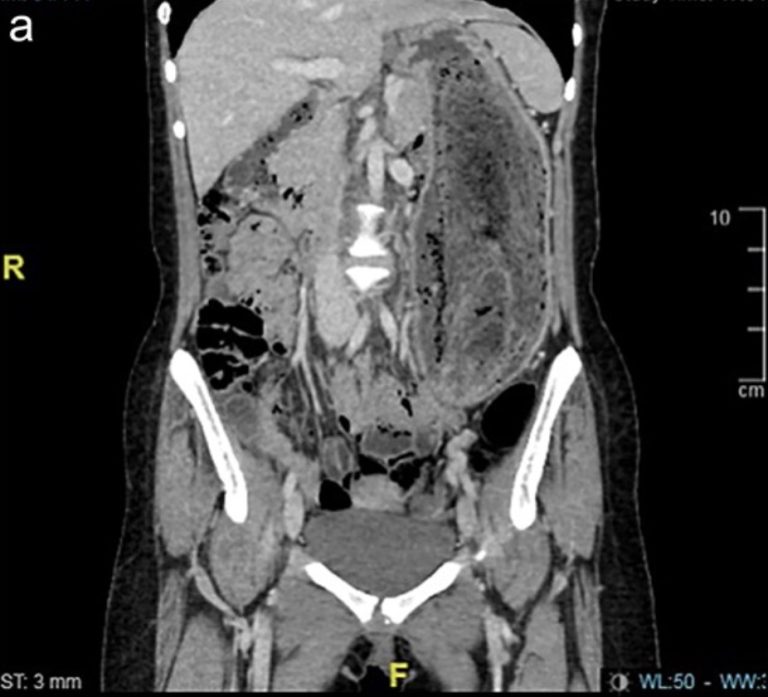

Thiếu nữ 17 tuổi liên tục đau bụng, nôn ói, bác sĩ sốc nặng khi phát hiện "bí mật" đáng sợ- Ảnh 1.

Trong khi tất cả các xét nghiệm trong phòng thí nghiệm đều bình thường, kết quả chụp CT xác nhận rằng búi tóc khổng lồ đã kéo dài từ dạ dày đến tá tràng.

Do kích thước của khối tóc, việc loại bỏ bằng phương pháp nội soi là không thể nên nữ bệnh nhân đã phải trải qua phẫu thuật mở dưới gây mê toàn thân.